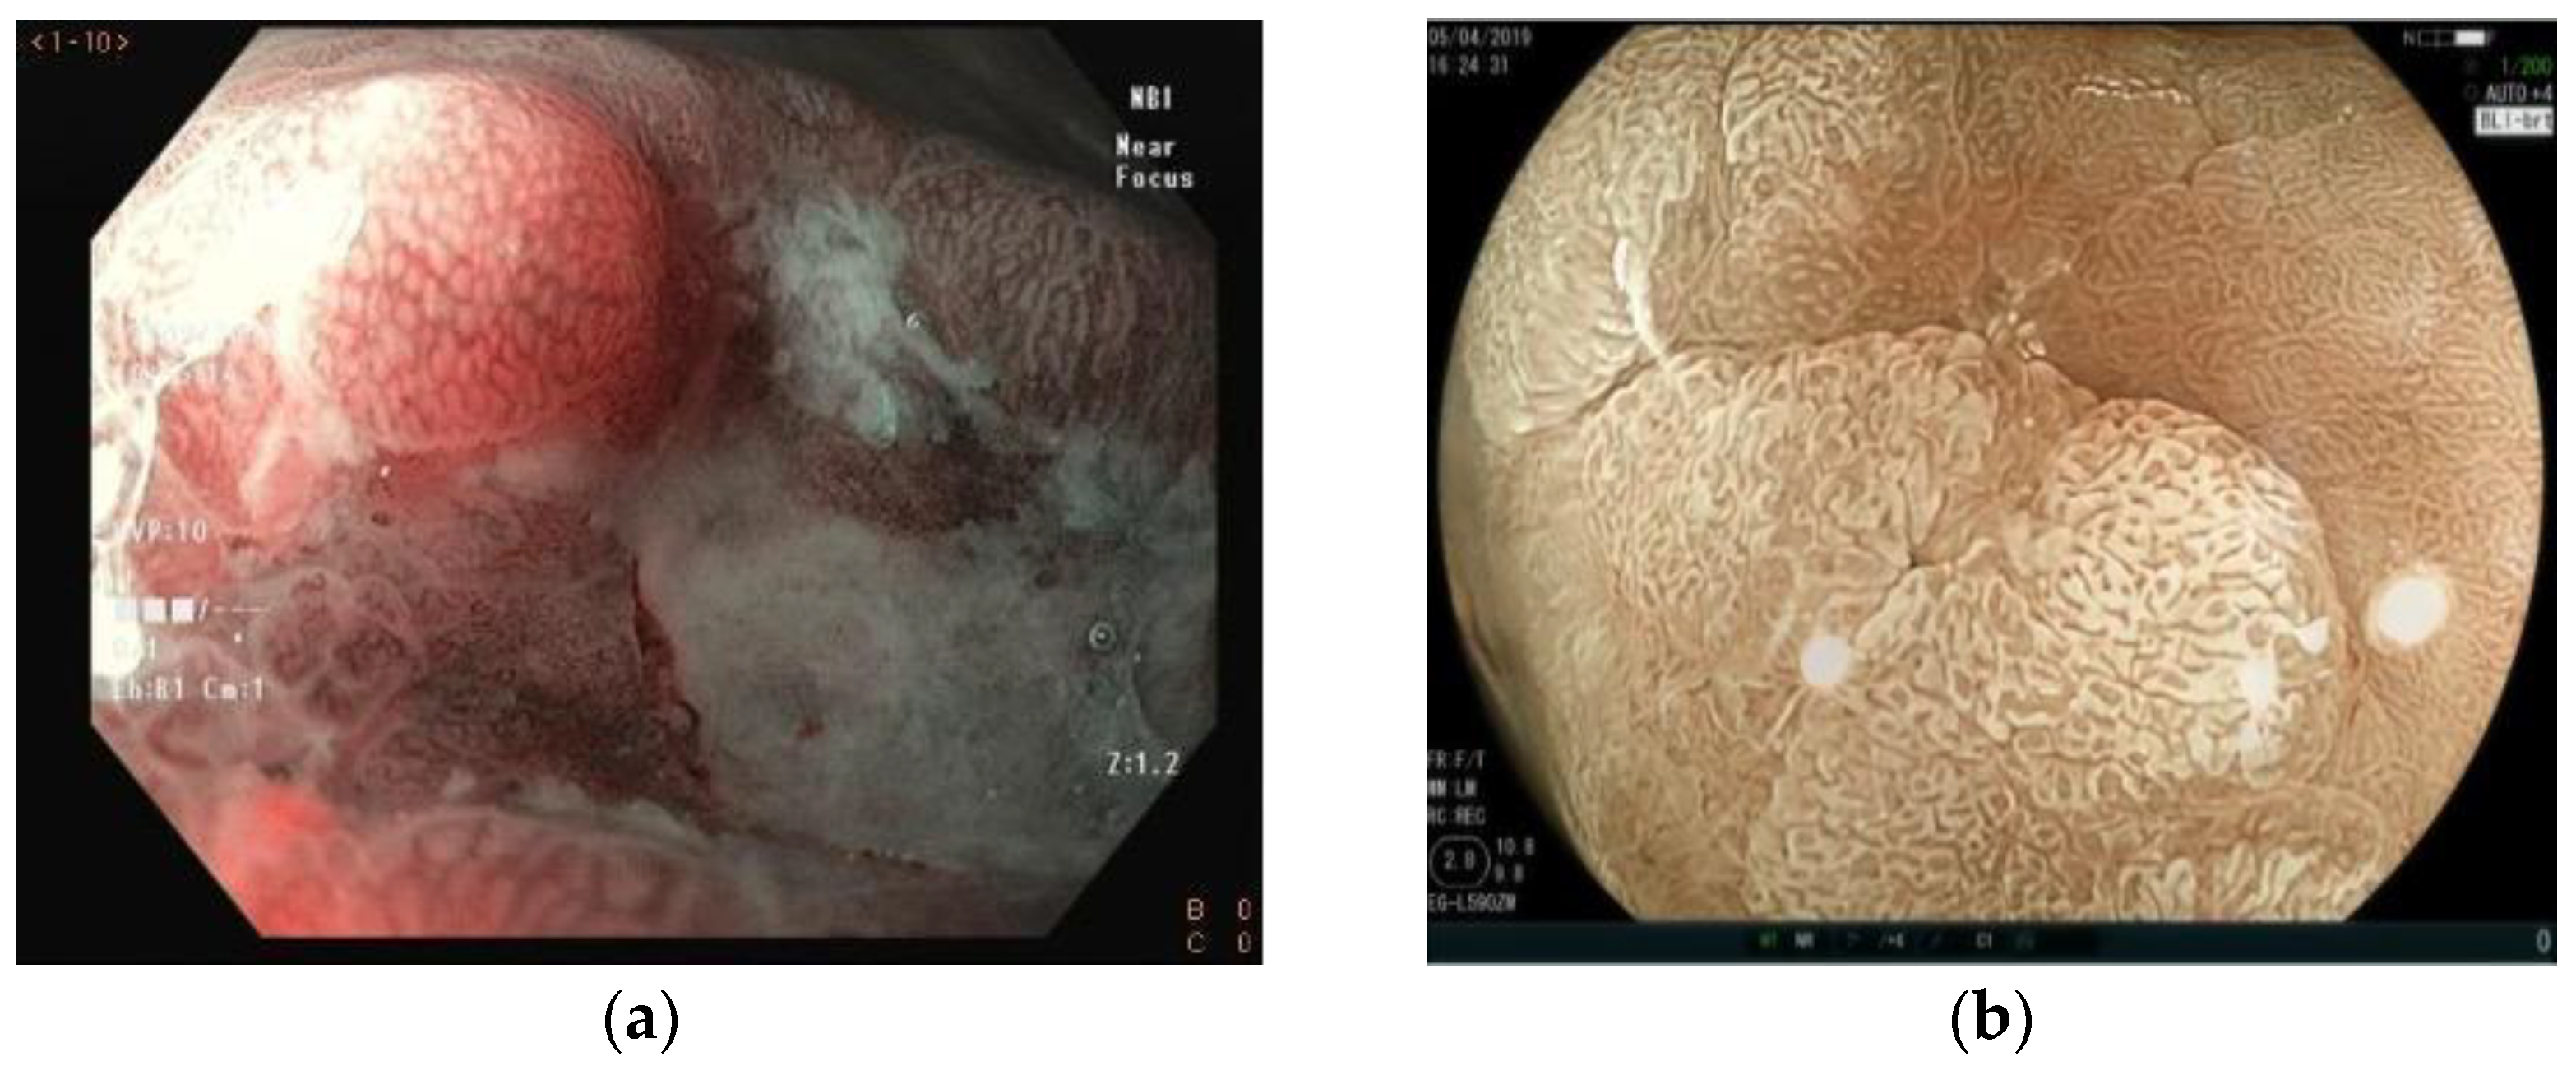

5. Virtual Chromoendoscopy

6. Magnifying Endoscopy